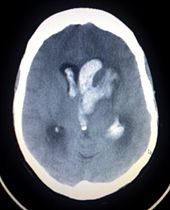

Stroke is diagnosed through several techniques: a neurological examination, CT scans (most often without contrast enhancements) or MRI scans, Doppler ultrasound, and arteriography. The diagnosis of stroke itself is clinical, with assistance from the imaging techniques. Imaging techniques also assist in determining the subtypes and cause of stroke. There is yet no commonly used blood test for the stroke diagnosis itself, though blood tests may be of help in finding out the likely cause of stroke.

For diagnosing ischemic stroke in the emergency setting:

- CT scans (without contrast enhancements)

- sensitivity= 16%

- specificity= 96%

- MRI scan

- sensitivity= 83%

- specificity= 98%

For diagnosing hemorrhagic stroke in the emergency setting:

- sensitivity= 89%

- specificity= 100%

- sensitivity= 81%

For detecting chronic hemorrhages, MRI scan is more sensitive.